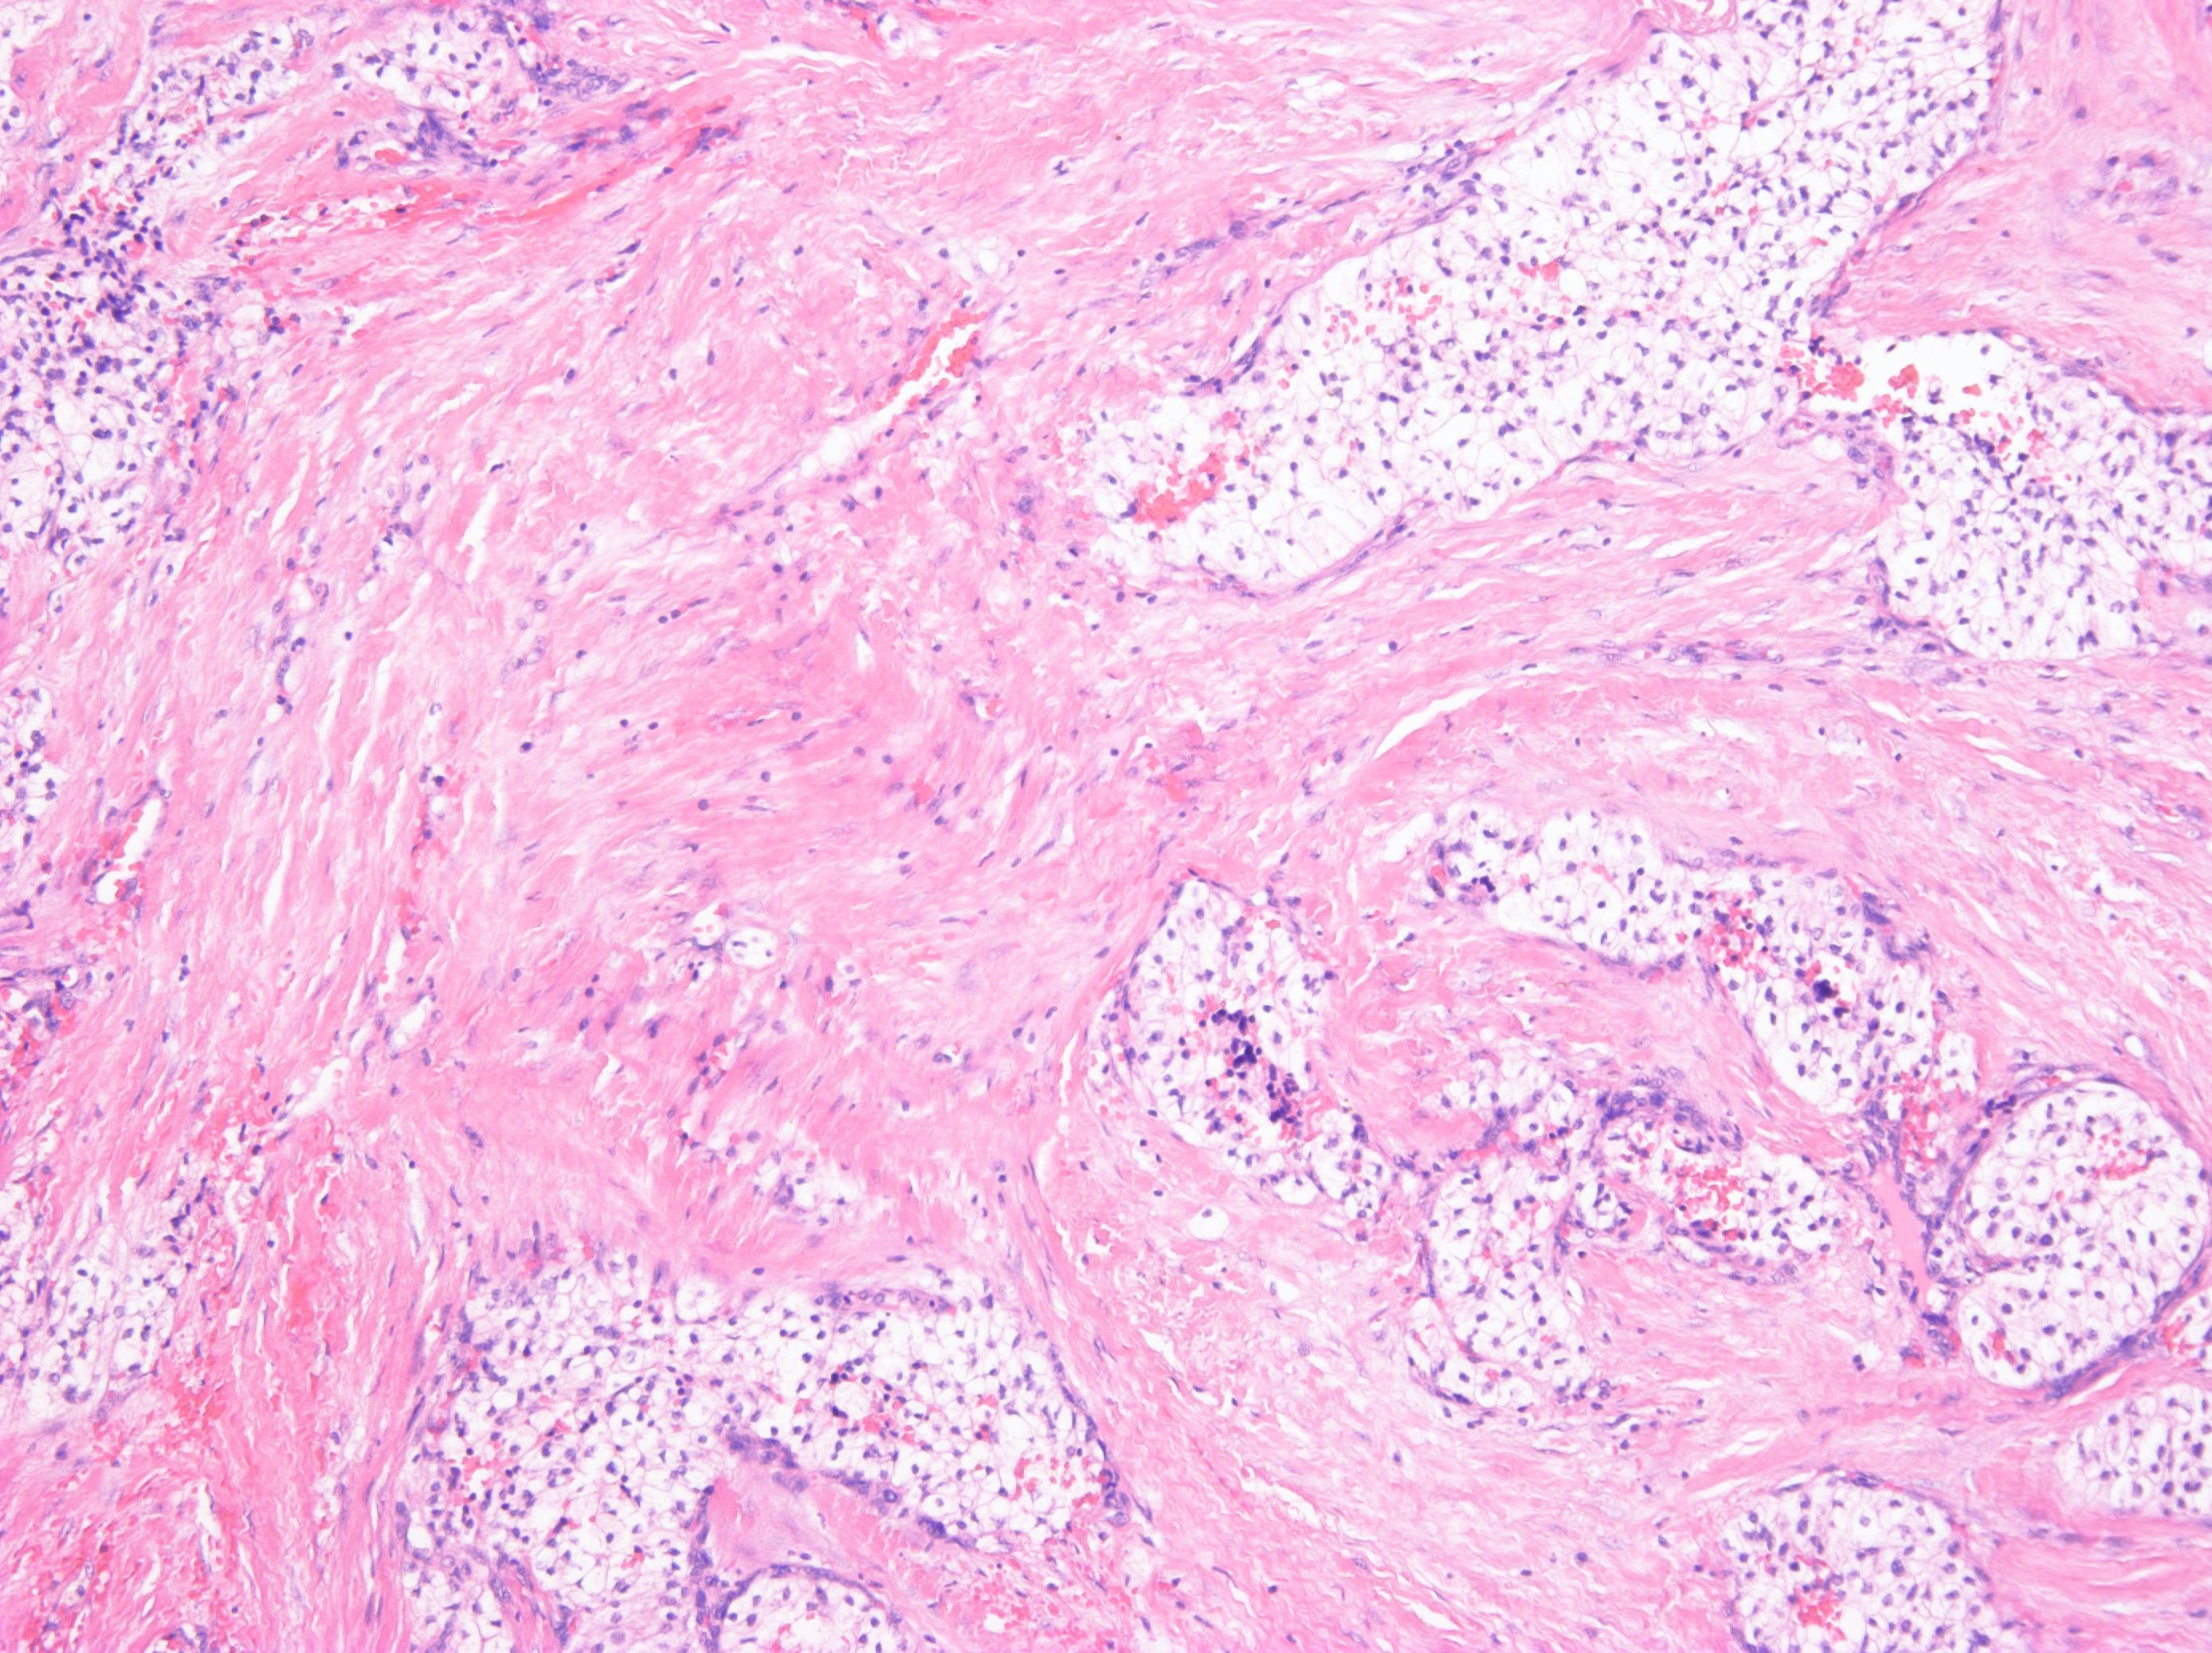

Consensus grade: Renal cell carcinoma with leiomyomatous stroma

Since there is a lot of pink stroma, this is probably thought to be clear cell renal cell carcinoma with leiomyomatous stroma but the photos show a stroma which looks fibrous to me so garden variety clear cell renal cell carcinoma is a better diagnosis for the photos. |

hard to be sure the stroma is muscle in these images |

Kidney tumor, male 62-year-old. Tumor well circumscribed, yellow color with gray strands on gross section. Tumor composed of clear cell elements resembling cells of typical clear cell RCC. Fibroleiomyomatous stroma was prominent. No sarcomatoid changes were present.

Dg: Renal cell carcinoma with (fibro)leiomyomatous stroma